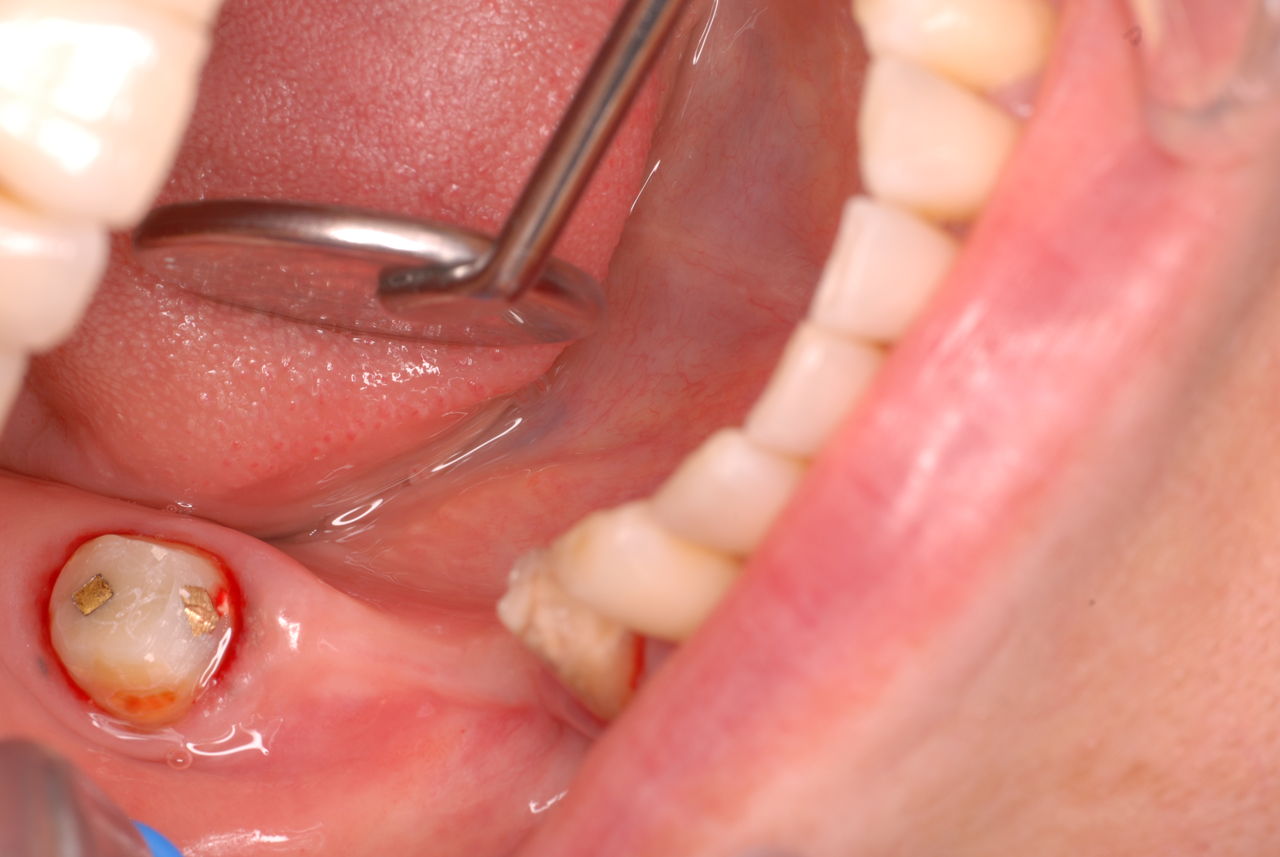

お口の中から差し歯、入れ歯、詰め物を追放しましょう!

口の中の病気を治し、病気を興さない医療を目指します。

二度とお口の中へ変なものを入れなくても済むように

予防に精進いたしましょう!安全な矯正、美容を目指しましょう!